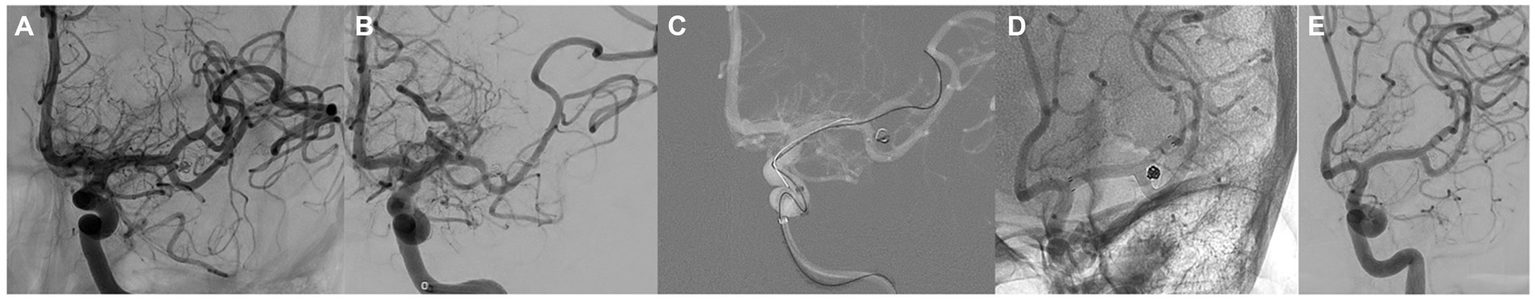

Intraprocedural complications occurred in four cases (8%), all of them in non-ruptured aneurysms. One patient (2%) presented with parenchymal hemorrhage with an mRS score of 2 at the 12 months follow-up visit. In one case (2%), acute branch occlusion of the middle cerebral artery was resolved by angioplasty and implantation of an Atlas stent with an mRS score of 1 at 12 months follow-up (Figure 2). A patient (2%) presented with vasospasm, resolved by local pharmacological treatment (vasodilators and glycoprotein IIB-IIIA inhibitors), without clinical repercussions (12-month follow-up mRs score, 0). One patient (2%) presented with fluctuating motor aphasia with negative neuroimaging findings and spontaneous resolution without neurological repercussions during follow-up. The final neuromorbidity at 12 months follow-up was 4%.

Figure 2

(A) Angiography showing an aneurysm of the bifurcation of the middle cerebral artery partially occluded by coiling. (B) post-SVB implantation control showing obstruction of the upper branch of the bifurcation. (C) Angiographic control after implantation of an Atlas stent showing reopening of the artery. (D) Angiographic control at 12 months showed complete occlusion of the aneurysm and patency of the upper branch of M2.